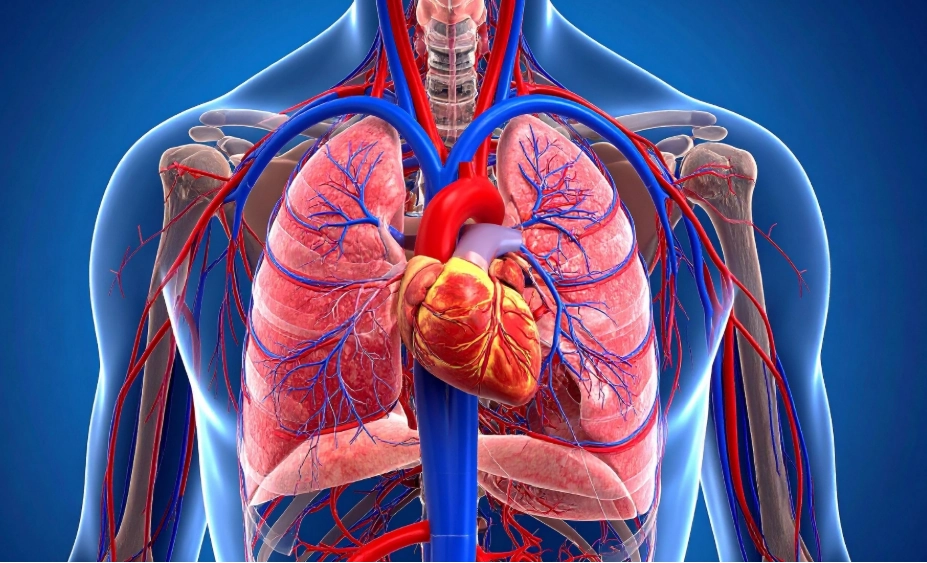

Giải phẫu X quang Phổi cơ bản

16/03/2026